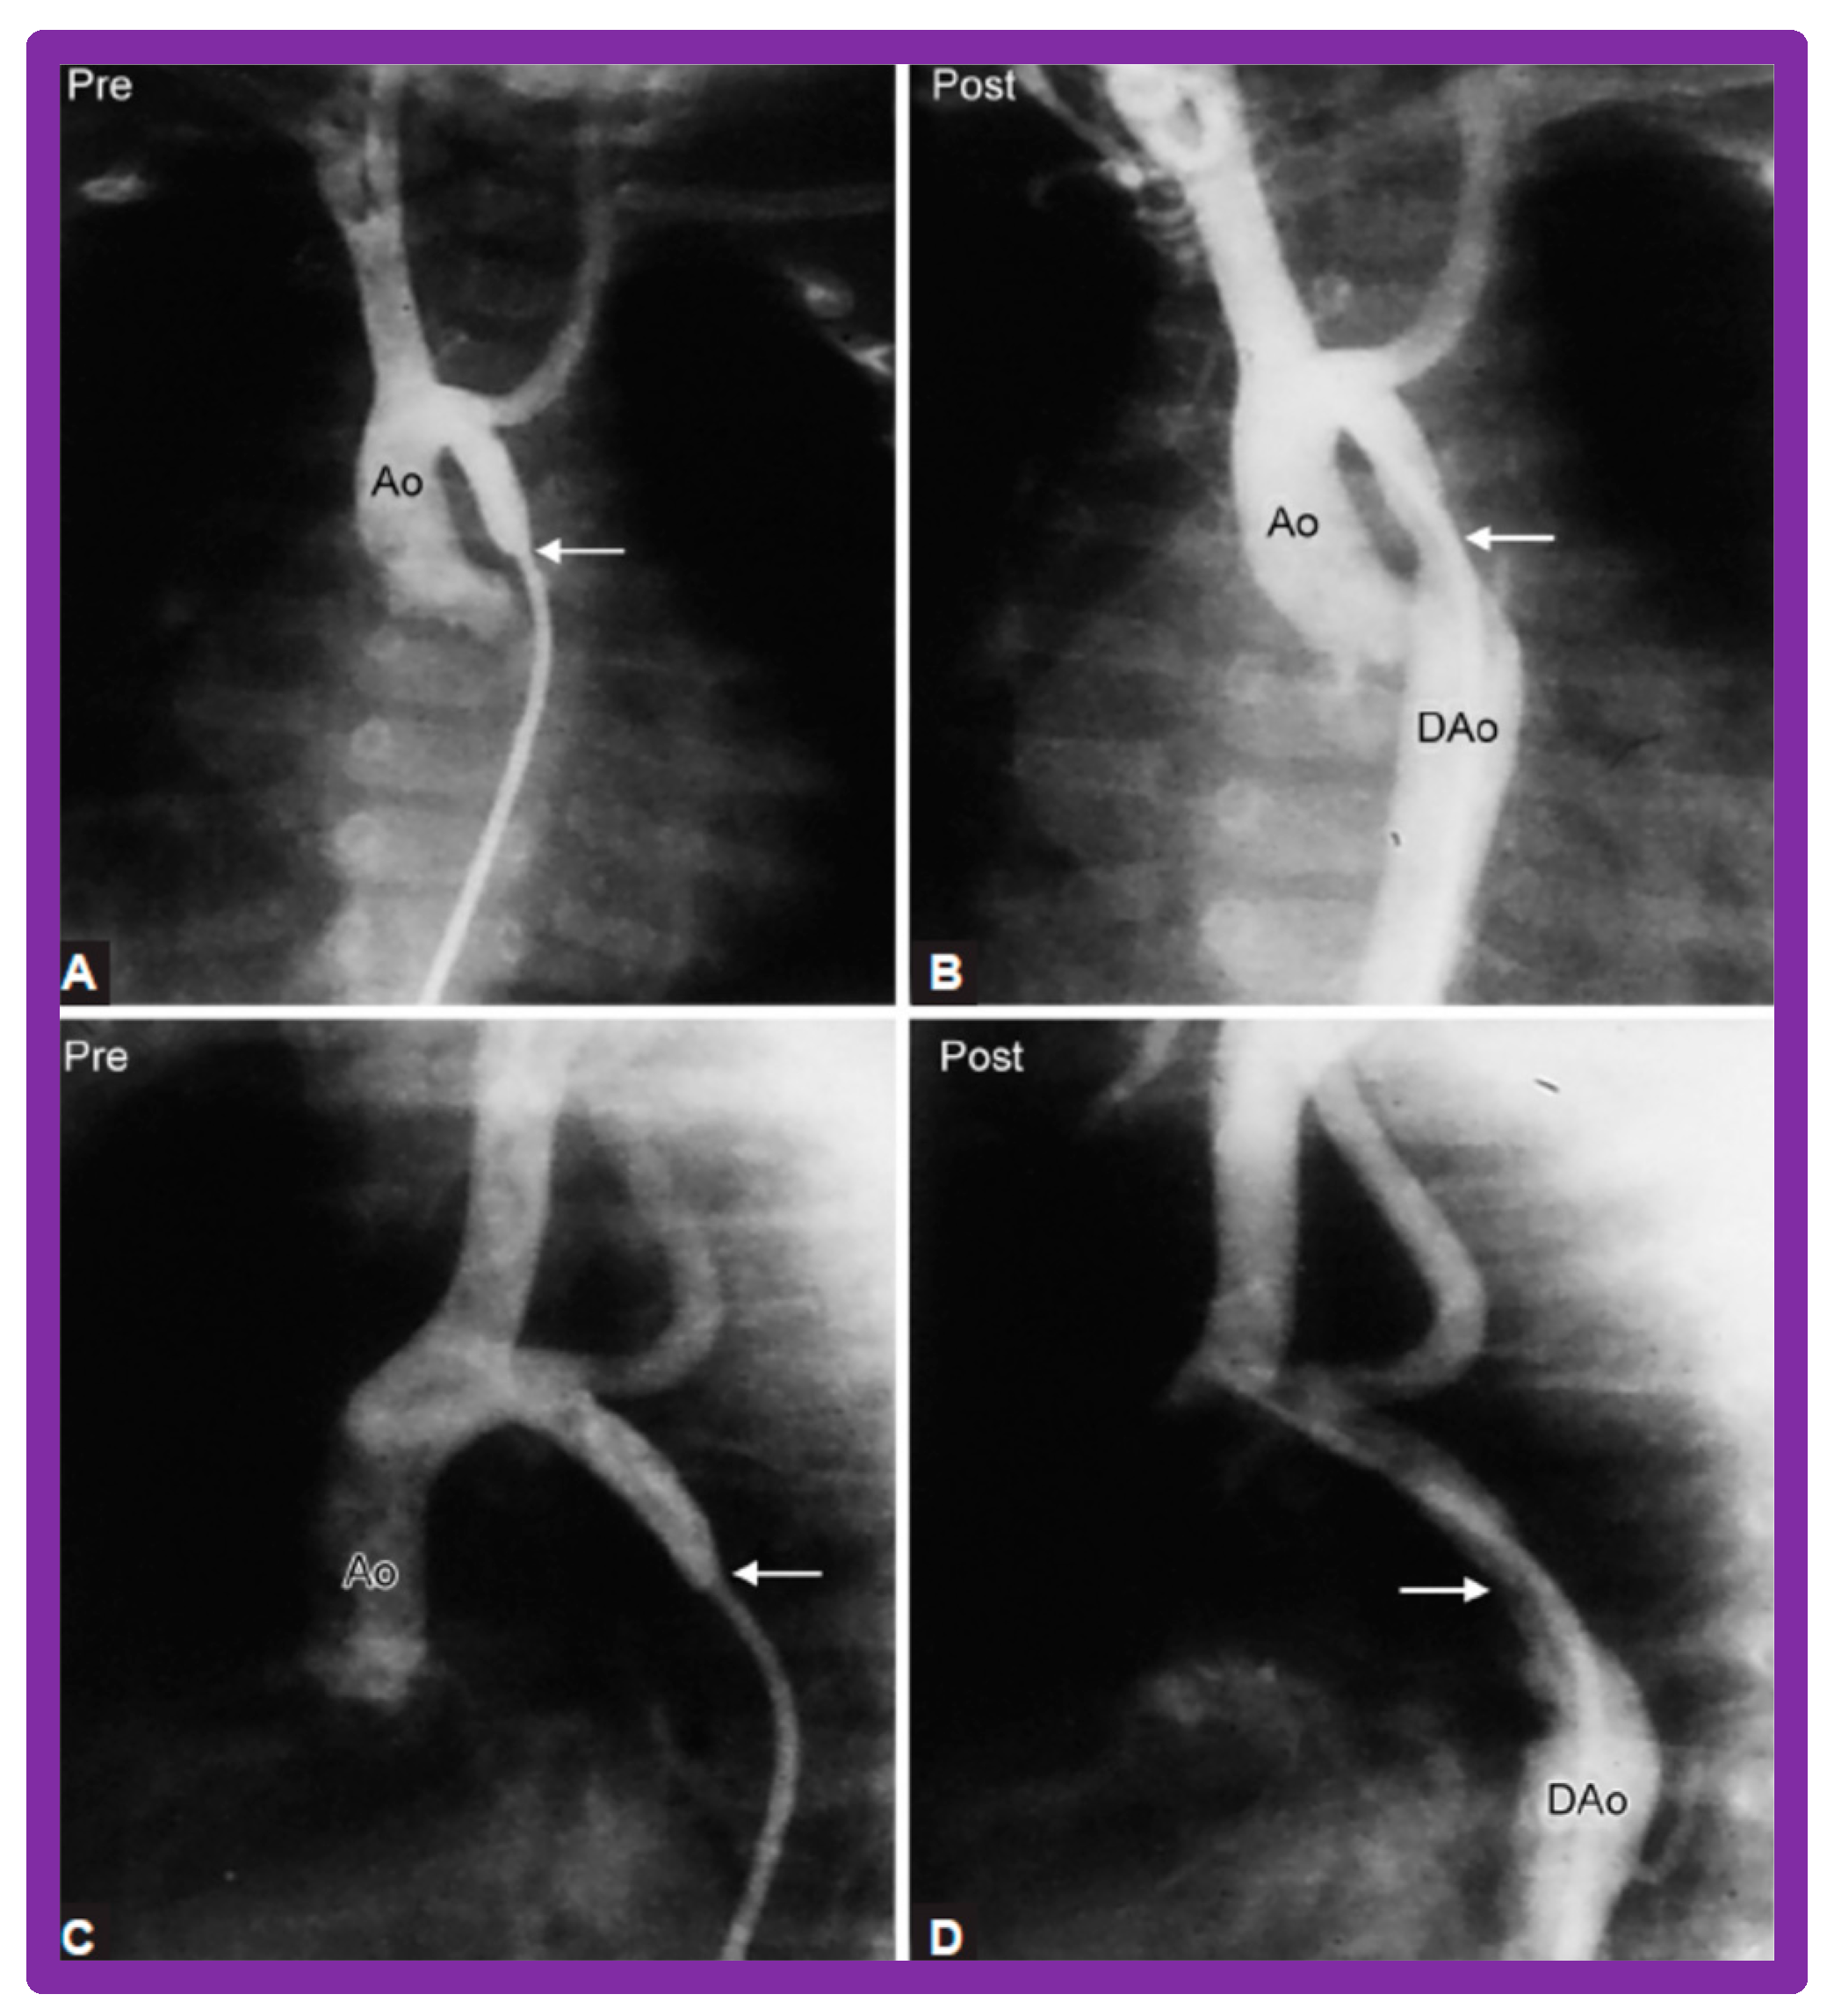

4.4. Aortic Coarctation, Postsurgical

5.4. Aortic Coarctation, Postsurgical

6. Long-Term Results